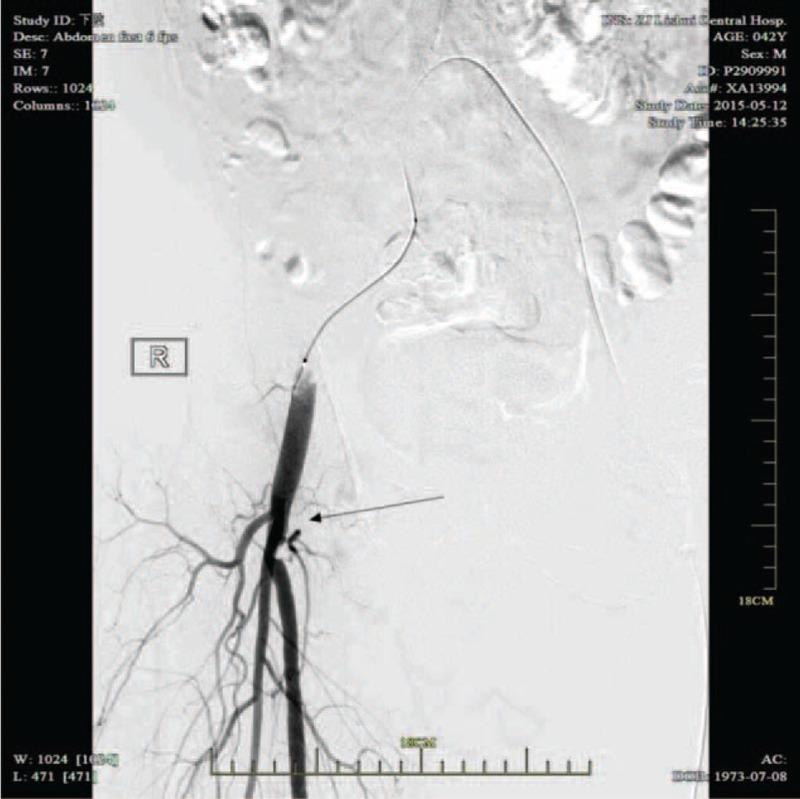

Double-lumen catheters have been used widely to obtain temporary access in patients who are in need of acute hemodialysis (HD) because of acute renal failure. Several complications are associated with the insertion of these catheters, including bleeding, infection, injuries to arteries, and deep venous thrombosis. An arteriovenous fistula (AVF) is a rare but significant complication following catheterization for temporary HD. Herein, we present a case of AVF associated with leg swelling 6 months after the removal ofa double-lumen HD catheter. We describe a special case of a 42-year-old man who experienced acute renal failure secondary to diabetic ketoacidosis (DKA). A 12-Fr dialysis catheter was inserted in the right femoral vein. Six months after catheter removal, the patient was admitted for pain and swelling in the right leg. Color Doppler ultrasound and three-dimensional computed tomography (CT) revealed an AVF between the right femoral vein and the right femoral superficial artery. The fistula was repaired successfully by vascular surgeons. This case highlights that an AVF is a rare but significant complication after catheterization for temporary HD. The nephrologist should be wary of the potential of this complication and perform clinical and medical examinations at the insertion and removal of temporary HD catheters.

双腔导管已被广泛用于因急性肾衰竭而需要进行急性血液透析(HD)的患者,以获得临时通路。这些导管的插入会引发多种并发症,包括出血、感染、动脉损伤和深静脉血栓形成。动静脉瘘(AVF)是临时HD导管插入术后一种罕见但严重的并发症。在此,我们报告一例在拔除双腔HD导管6个月后出现与腿部肿胀相关的AVF病例。我们描述了一名42岁男性的特殊病例,该患者继发于糖尿病酮症酸中毒(DKA)而出现急性肾衰竭。在右股静脉插入了一根12F透析导管。导管拔除6个月后,患者因右腿疼痛和肿胀入院。彩色多普勒超声和三维计算机断层扫描(CT)显示右股静脉与右股浅动脉之间存在AVF。血管外科医生成功修复了瘘管。该病例突出表明,AVF是临时HD导管插入术后一种罕见但严重的并发症。肾病科医生应警惕这种并发症的可能性,并在插入和拔除临时HD导管时进行临床和医学检查。